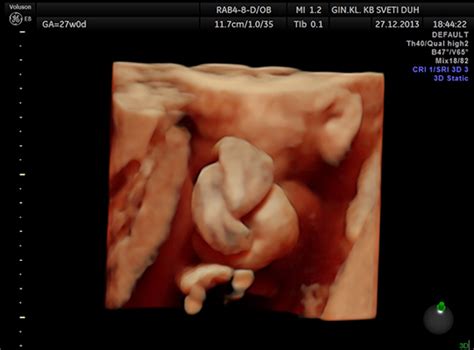

Diagnosing an Umbilical Cord in Knot

Diagnosing an umbilical cord in knot typically involves ultrasound examinations. Ultrasound technology allows healthcare providers to visualize the cord and detect any knots or entanglements. Regular prenatal check-ups and ultrasounds can help identify this condition early in the pregnancy.